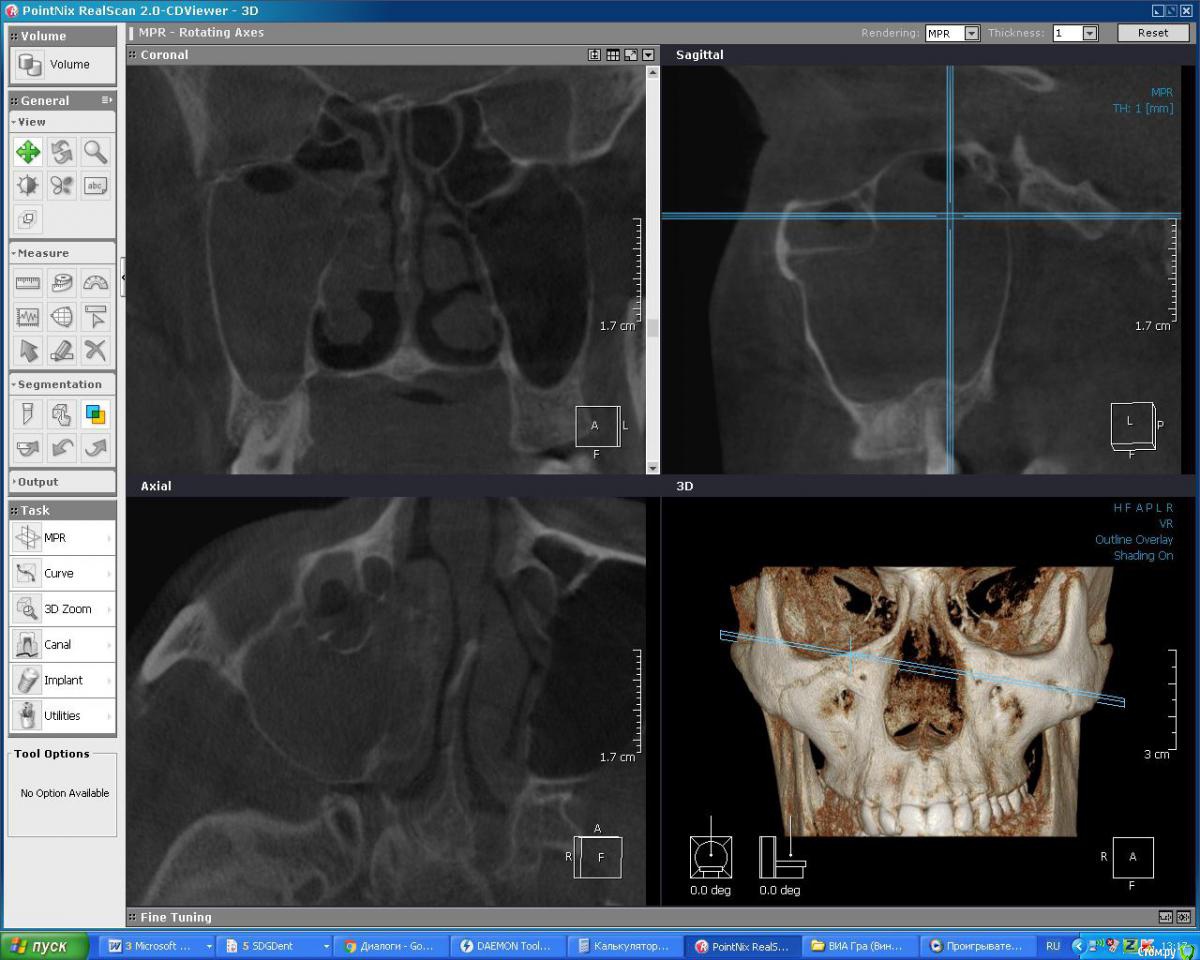

DoktorDre Опубликовано 6 декабря, 2015 Поделиться Опубликовано 6 декабря, 2015 Всем доброго времени суток! Ситуация - 10 дней назад удалил 1.8 не сильно кариозный. Соустья вроде не было. Но шнайдерову видел. Зашил. Через неделю - лунка пустая, отделяемого нет. Но есть лёгкий альвеолит.промыл,хг и в лунку метрогил.на след день все прошло.сегодня боли, голова болит, субфибрильная. Направил на кт. Вот оно.Чтото у меня ни разу такого не было, жидкости я не вижу в пазухе.назначил зифактор 500.что делать то? Ждать, пункция? к3.bmp Ссылка на комментарий

Евгений Ходыкин Опубликовано 6 декабря, 2015 Поделиться Опубликовано 6 декабря, 2015 По кт сообщение то видно?? Тоже кажется, что 1.8 не при делах... 2 Ссылка на комментарий